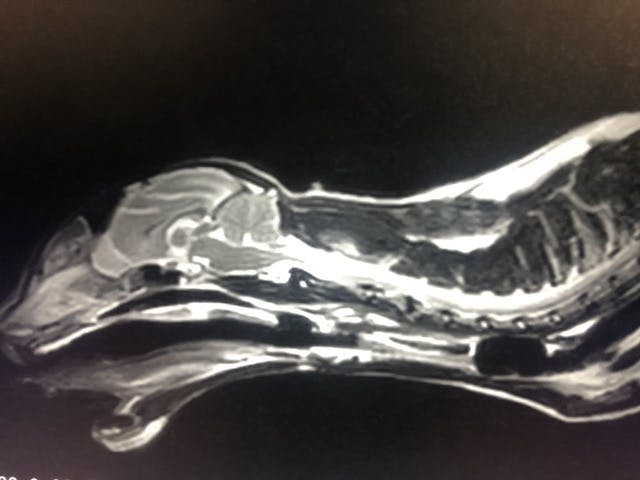

その後、糖尿病は順調にコントロール可能となり、先々インスリンから離脱できるという話も出ており家族皆んなで喜んでいました。しかし、8月23日に急な右半身の麻痺が始まり夕方には立てなくなってしまって、、病院の先生もリンパ腫の脊髄への転移なのかと頭を悩ませる限りでした。 正直MRI検査をやらないことにはわからないと言われ麻酔の不安をかかへながら検査を翌日してもらうと髄膜炎?という病気が疑わしいということで治療を開始しました。